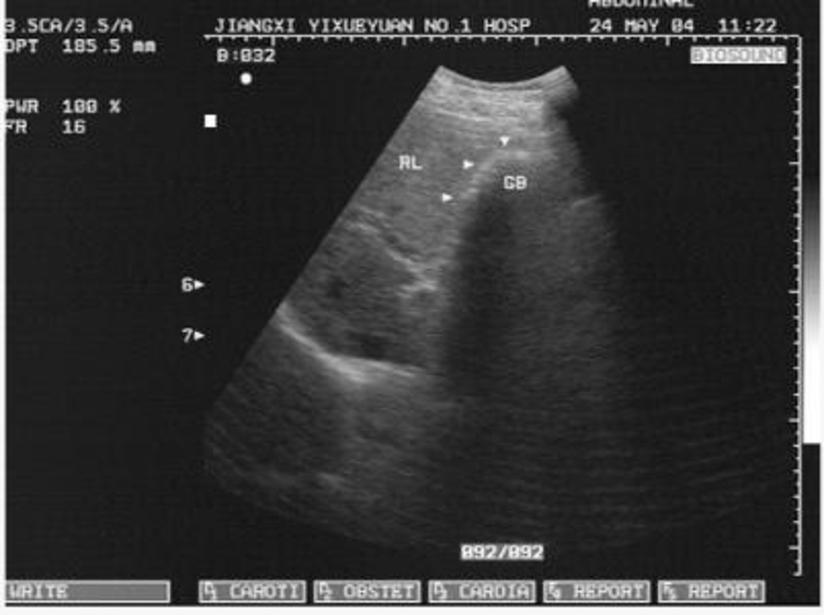

B超检查子宫内膜炎表现 生活保健 靓范儿